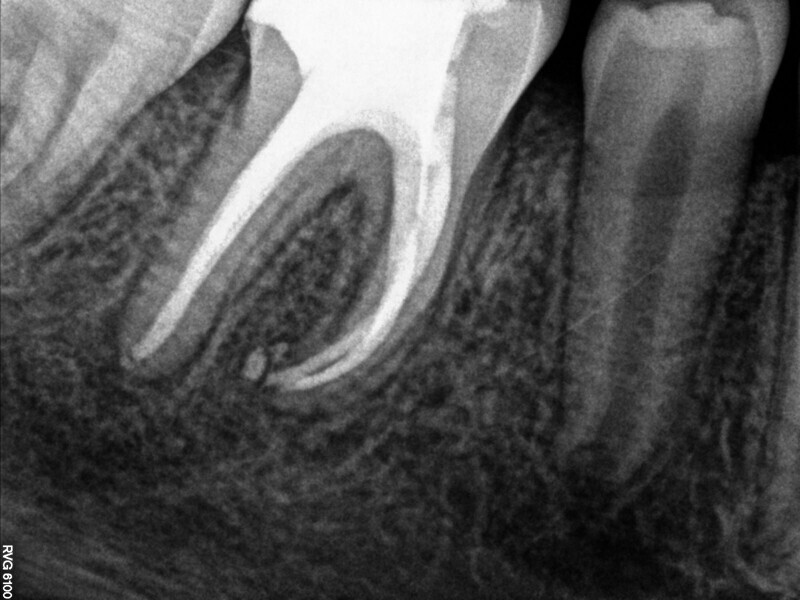

Fig. 1: Conventional radiograph of an endodontically treated tooth #11 and cold-sensitive tooth #12 compared with CBCT imaging showing the presence of a large apical bone defect (taken at a two-day interval).